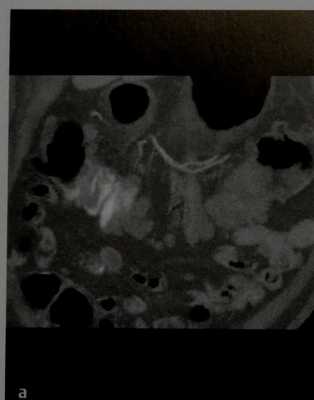

У пациента 64 лет, перенесшего субтотальную гастрэктомию по поводу МРЖ, через два дня после операции отмечено снижение артериального давления.

(а-г) При КТ выявлено умеренное количество крови в брюшной полости (*), гиперденсивное перигастральное образование, расположенное вдоль большой кривизны культи желудка, а также гиперденсивная гематома в левом поддиафрагмальном пространстве, распространяющаяся до полости малого таза (указатели). В перигастральной зоне гематомы определена тонкая линейная гиперденсивность, совпадающая с ходом коротких артерий желудка (стрелка, а).

Заключение КТ: возможные ишемические изменения культи желудка вследствие кровоизлияния из короткой артерии желудка и ассоциированный внутрибрюшной гемиперитонеум. Экстренная диагностическая лапаротомия подтвердила послеоперационное кровотечение из культи короткой артерии резецированного желудка.